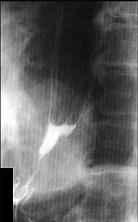

问题 女性,65岁,进行性吞咽困难半年,消瘦,钡餐检查如图,最佳的诊断是()

选项 A.贲门失弛缓症 B.食道静脉曲张 C.食管鳞状(上皮)细胞癌 D.贲门癌 E.返流性食道炎

答案 C